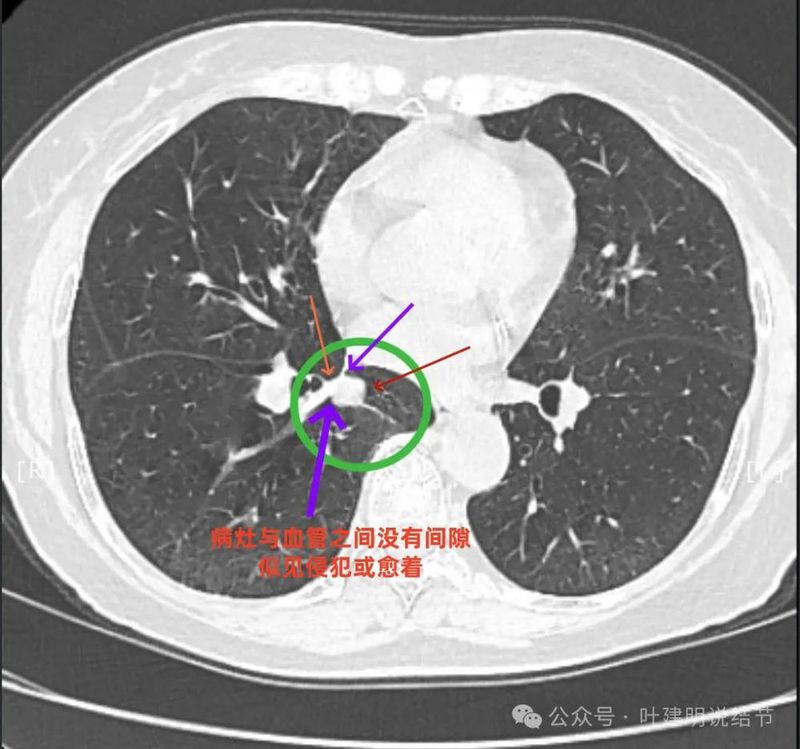

上图这个层面感觉病灶与肺血管之间没有明显间隙,似像侵犯或愈着的样子。

结节边缘区域与血管之间又有间隙了的。

与血管关系近。

边缘区域与下肺静脉间隙不太清楚。